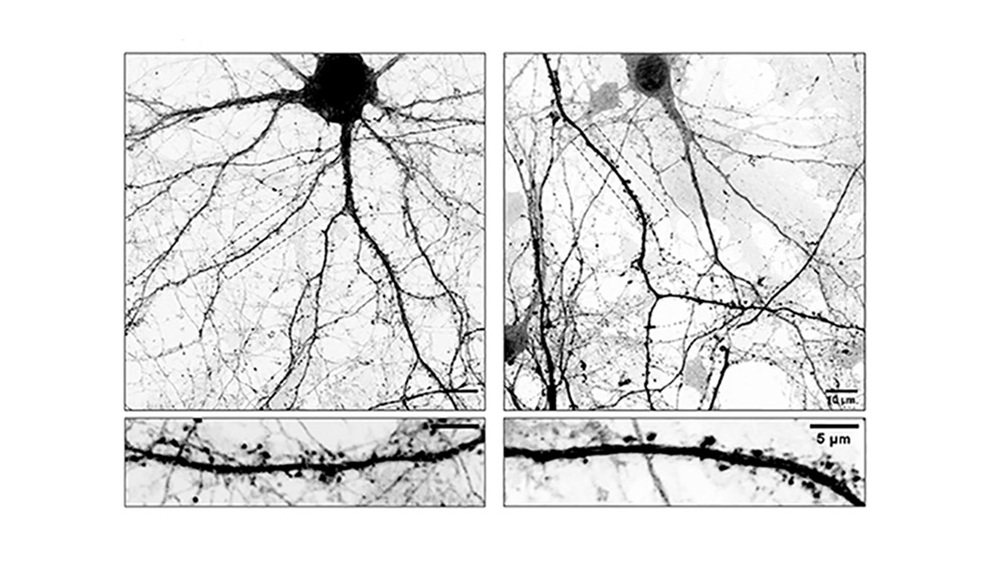

Izqu neuronas normales. Der: neuronas modificadas con L-Dopa. Foto: Conicet.

En este contexto, el grupo liderado por Gastón Bisig, investigador del Ciquibic (Conicet–UNC), propuso que la acción de la L-Dopa podría extenderse más allá de su función química tradicional. “El problema es que cuando L-Dopa se integra en estos microtúbulos los hace menos dinámicos afectando su ingreso a las espinas dendríticas, estructuras que funcionan como las ‘antenas’ receptoras de la neurona donde se forman las sinapsis. Como consecuencia directa de esto, las neuronas comienzan a perder espinas, claves para la comunicación neuronal. Entendemos que esta inestabilidad sináptica podría explicar algunas de las complicaciones que aparecen luego de un tiempo prolongado de tomar L-Dopa”, afirmó Bisig.